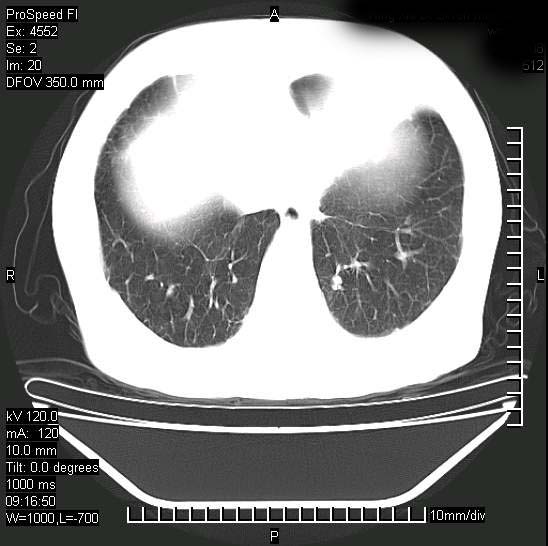

标题: CT15528:女性,79岁,近几日晚上高热,39度,仍咳少量血 [打印本页]

十几年前曾患肺结核,一周前突咳血约100ml,中性粒细胞稍高,诊断两上肺陈旧结核,下肺炎症,给予抗炎治疗,近几日晚上高热,39度,仍咳少量血,4天前ct及今天ct上传。

今天ct

短短几天内,病变范围明显增多扩大,以左侧明显,而且双侧出现胸水,还是考虑感染.

短短几天内,病变范围明显增多扩大,以左侧明显,而且双侧出现胸水,我更多考虑左侧中心性肺癌并并阻塞性不张及肺炎,炎症变化也太快了!

继发性结核感染加重。左侧合并有支气管内膜结核。

无论是肿瘤还是炎症4天的时间都发展够快的,并且还在治疗中,如果说是左肺癌那么右肺的病变不好解释,本人更加倾向于炎症,左肺舌叶支气管被痰栓或血凝块堵塞,造成阻塞性肺炎。

1)两肺结核并感染。2)不排除左肺上叶中央型肺癌并阻塞性肺炎、肺不张可能;建议行纤支镜检查。3)右肺门及纵隔淋巴结肿大。4)双侧胸腔积液。

陈旧性肺结核及左下肺不张,咯血后肺部感染,双胸腔积液,高热可能与痰液引流不畅有关。